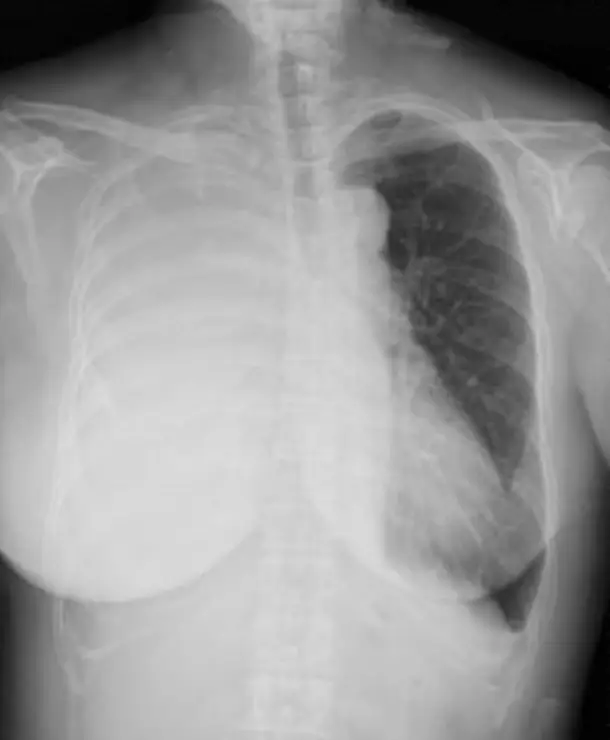

病人主訴呼吸喘及右胸痛,胸部X光檢查結果如圖 (八),下列何者是造成胸部 X 光右胸全白最可能的原因?

圖為正位(frontal/PA view)胸部 X 光:

- 右側胸腔呈現完全性不透明化(complete opacification of right hemithorax),整個右肺野呈現均勻白色影像。

- 縱隔(mediastinum)向左側移位:氣管可見輕微偏向左側,心臟輪廓亦向左偏移,顯示右側胸腔容積增加(volume expansion)。

- 右側肋骨間隙(intercostal spaces)略為寬闊,同樣提示右側胸腔佔位效應(mass effect)。

- 左側肺野透明度正常,未見明顯異常。

- 右側橫膈輪廓消失(obscured),肋膈角(costophrenic angle)無法辨識。

影像解讀:縱隔向對側(左側)移位 + 右胸全白,此組合最符合大量肋膜腔積液(massive pleural effusion)。若為右肺塌陷(collapse/atelectasis),縱隔應向同側(右側)移位;若為右肺實質化(consolidation),一般不會造成完全性胸腔不透明且縱隔移位不明顯。